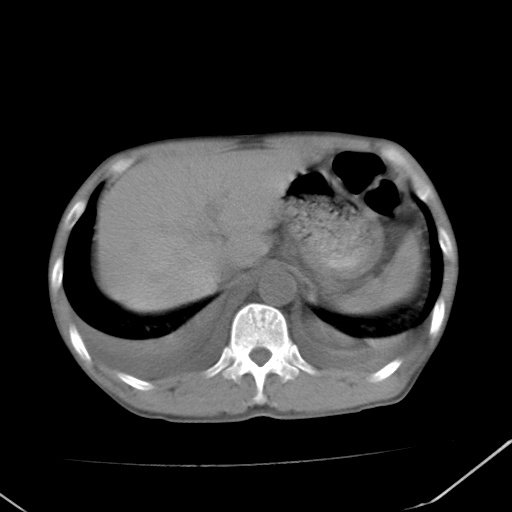

男、42岁、咯血3天。既往有甲亢、贫血、血尿蛋白尿史多年。血象:wbc:6.   中性粒:70.6%。

谢谢各位指导。刚才急查肾功能结果:肌酐1000多。尿毒症。

肾性肺水肿 双侧胸腔积液

由慢性肾功能衰竭引起肺部间质性肺炎。